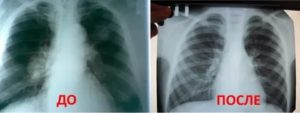

Достоверная визуальная диагностика плевральных шварт возможна только если соединительно-тканные образования больше 1 см в толщину. В противном случае тень от спаек накладывается на ткань легкого и не видна на рентгенограмме. При указании на характерные жалобы, которые возникли и сохраняются после перенесенного плеврита, требуется проведение дополнительных исследований таких, как:

Для обнаружения легочных заболеваний в первую очередь используется флюорография. Эту процедуру необходимо проводить ежегодно, в основном она направлена на выявление ранней стадии туберкулеза. Однако опытный рентгенолог может выявить на снимке образовавшиеся плевральные спайки, которые выглядят тенями. Причем форма их не меняется в зависимости от вдоха и выдоха.

При необходимости дополнительно назначается рентген. Как правило, спайки располагаются в нижней части легкого. При этом будет более темная картинка, а также может быть частичная деформация грудной клетки и диафрагмы.

На снимках тяжи выглядят затемненными участками легочного поля с усиленным сосудисто-соединительнотканным рисунком. При множественных поражениях определяются диффузные затемнения. Также возможно снижение высоты стояния ребер, уменьшение межреберного пространства и смещение органов.